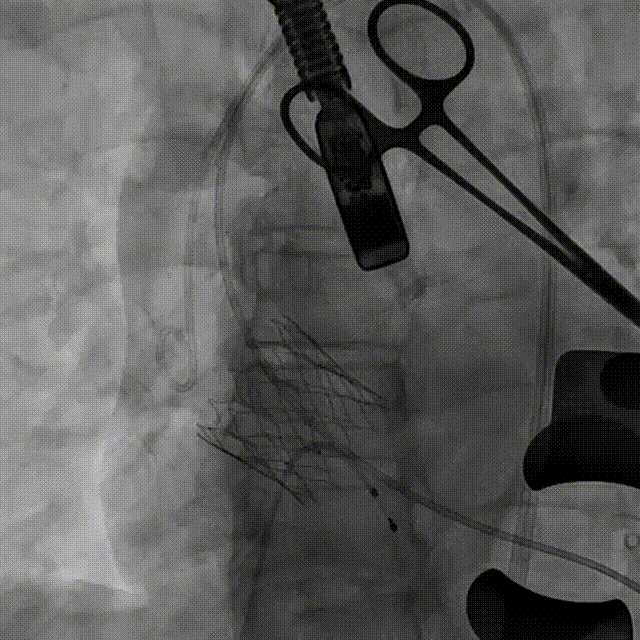

最终造影,瓣膜位置可,几乎无瓣周漏

本例手术中,患者瓣环直径达29.7mm,且为单纯反流结构,存在瓣膜锚定困难、释放位置要求高等技术挑战。高永生教授团队选用的ScienCrown瓣膜凭借其“全释放/全回收”功能,突破了既往瓣膜部分可回收的操作限制,显著提升了植入过程的调控精度与容错率,从而保障了手术安全。其独特的直筒型设计使瓣膜能够实现多节段锚定,提供更稳固的径向支撑力。本例植入TA32号瓣膜,oversize仅约7.74%,依旧能够提供充足锚定。